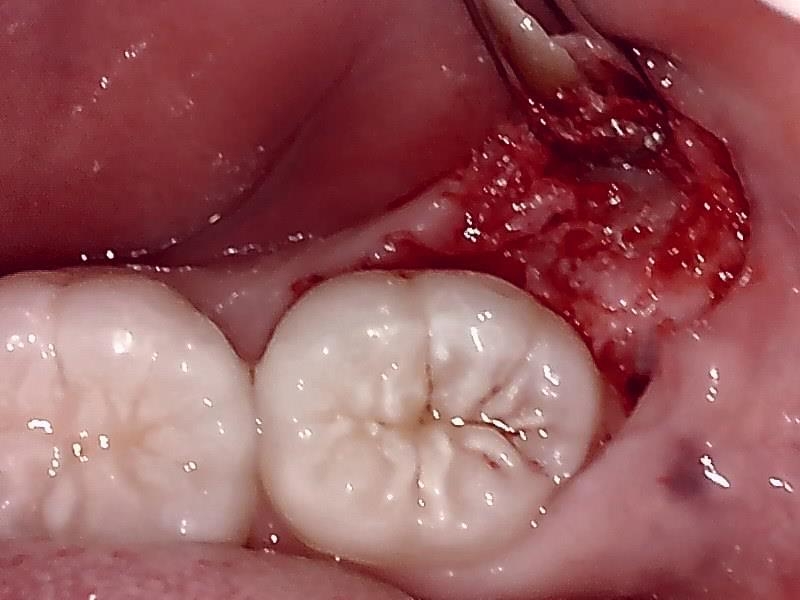

切開して歯肉剝離する。

歯冠を明示する。